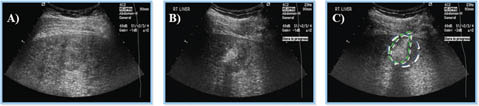

An accurate diagnosis and proper staging assessment are necessary to determine the optimal treatment method for the individual patient with HCC. A liver tumor is usually detected by imaging and its histology confirmed by tissue analysis (55). The various imaging methods include ultrasound (US), which is recommended every six months as a non-invasive low radiation cost-effective screening technique on high-risk patients, and computed tomography (CT) and magnetic resonance imaging (MRI), which are complementary techniques that detect and characterize the different nodules that develop in cirrhosis (Figure 3) (5659). Although there are at least seven staging systems for HCC, the Barcelona Clinic Liver Cancer (BCLC) classification is the most widely and accepted staging system used (Figure 4) (55, 60, 61). The BCLC classification system (Table 1) includes guidelines for the treatment of HCC and has been endorsed by the European Association for the Study of the Liver (EASL), European Organization for Research and Treatment of Cancer (EORTC) and the American Association for the Study of Liver Diseases (AASLD) (60, 62). This system stages an individual as having very early, early, intermediate, advanced, and very advanced (terminal) HCC based on tumor burden, severity of liver disease and his/her performance status matching the recommended evidence-based treatment by the stage of liver tumor (55, 60).

Fig 3

Figure 3. Sensitivity of ultrasound as a surveillance tool for the detection of hepatocellular carcinoma. Ultrasound is recommended every 6 months in high-risk populations for monitoring the development of HCC, as well as in cirrhotic patients. Its sensitivity is around 77% and it can be complemented, if needed, with other imaging modalities, such as computed tomography or magnetic resonance imaging (59).